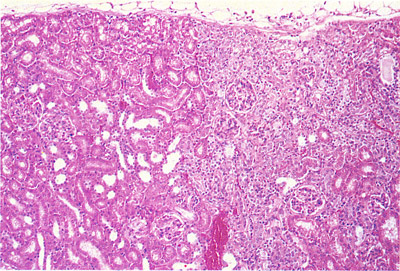

Figure 243. Infarct - Kidney